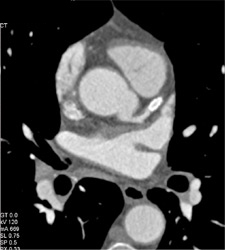

Patent Stent in LAD